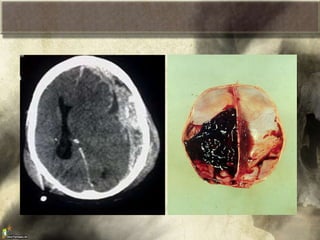

Hematoma

intraparenquimatoso

cerebral

Área hiperdensa,

intracerebral, de límites

bien definidos, que ha de

tener un volumen superior

a los 25 cm3 para que se

considere como lesión

masa.

Hematoma intraparenquimatoso cerebral Área hiperdensa, intracerebral, delímites bien definidos, que ha de tener un volumen superior a los 25 cm3 para que se considere como lesión masa.